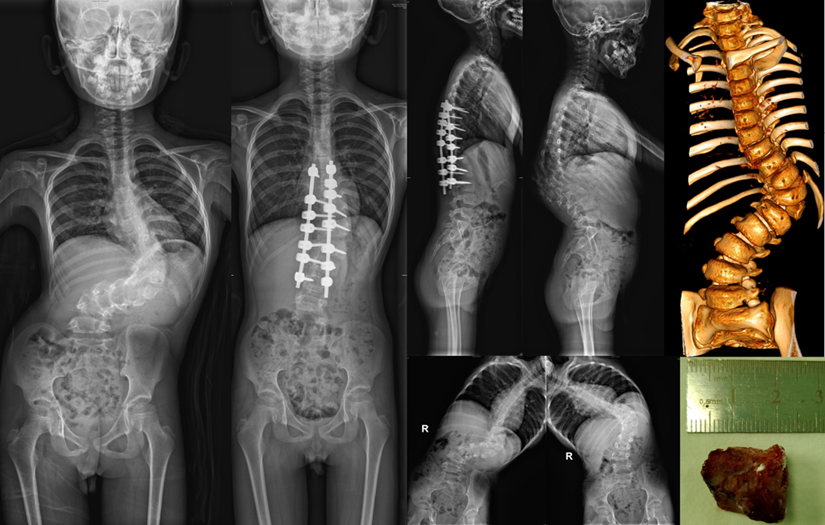

徐杨团队根据检查影像作了详实的分析和评估,决定将患者的T12半椎体切除,以较短节段固定进行畸形矫正。术后早期效果良好,患者身高由术前的1.29米纠正到术后的1.37米,剃刀背畸形得到明显纠正。“孩子手术后还需要持续佩戴支具和严密随访观察,等骨骼发育接近成熟的时候再次进行最终的融合手术。”徐杨说。

五年的持续跟踪治疗,更换了四副支具,随着孩子进入青春期,身高长到1.65米,畸形再次加重,支具治疗已经不能阻止畸形进展,出现了明显的躯干偏移。

今年3月,福建省立医院骨科与运动医学中心为患者做了第二次手术,基本矫正了畸形,融合节段延长,术后身高达到1.73米。